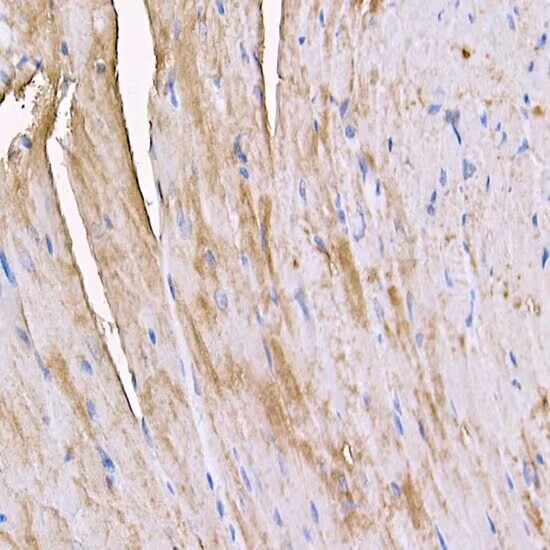

Immunohistochemistry of paraffin-embedded mouse heart using MYH4 antibody at dilution of 1:100 (40x lens).Perform high pressure antigen retrieval with 10 mM citrate buffer pH 6.0 before commencing with IHC staining protocol.